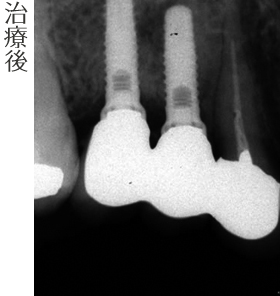

- インプラント(2本)

- 骨造成(GBR)

- インプラント上部セラミック冠 (2本)